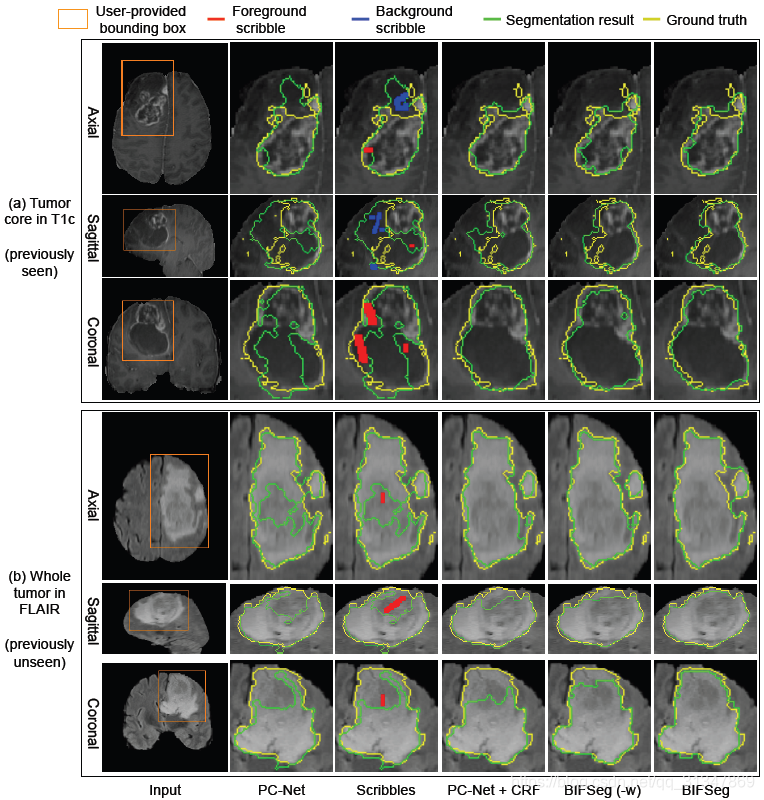

比较 BIFSeg 和 1)P-Net/PC-Net 的初始分割结果;2)用 CRF 处理之后的分割结果;3)BIFSeg(-w) 的分割结果(基于 Eq(1),所有像素的权重 w ( i ) = 1 w(i) = 1 w(i)=1),以及其他交互式分割方法:用于 2D 分割的 GrabCut,SlicSeg,Random Walks;用于 3D 分割的 GeoS,GrowCut,GrabCut 3D

2. 3D 图像分割

(2)Unsupervised Image-specific Fine-tuning:

基于 PC-Net 得到的初始分割结果,仍然用其他三种方式进行无监督的调整。

不管对于见过的还是没见过的图像,BIFSeg 仍然是表现最好的,其他两种方法相比初始结果有提升,但是不够好。

(3)Supervised Image-specific Fine-tuning: